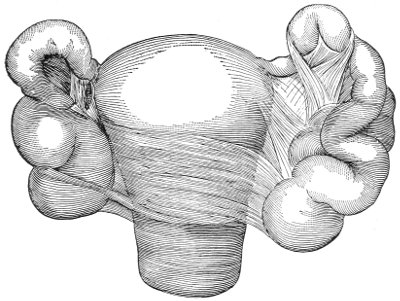

Cysts of the gland may be unilocular if formed at the expense of a single lobule of the gland, or multilocular if several lobules enter into their formation. These cysts may attain the size of the fetal head (Fig. 18).

Cysts of the gland or of the duct are formed by retention of the cyst-contents. The retention is due to occlusion of the duct, usually the result of inflammation. In some cases the duct remains pervious, and the retention is due to the altered character of the secretion of the gland, which becomes too viscous to pass, except under unusual pressure, along the duct.

These cysts contain clear yellow or chocolate-colored 42 fluid. The diagnosis of cyst of the vulvo-vaginal gland is usually not difficult. If we are in doubt in regard to the fluid character of the tumor, this may be determined with the exploring-needle.

Inguinal hernia, hydrocele of the canal of Nuck, cysts of the round ligament, and sacculated cysts of old hernial sacs may be mistaken for cysts of the vulvo-vaginal glands. In such cases, however, the tumor lies more in the upper and outer part of the labium majus, and extends to, and may be connected with, the external inguinal ring.

Cysts of the vulvo-vaginal glands should be treated by free incision and packing, or by extirpation. If the sac is emptied by the aspirator or by a small incision, it will refill. The best method is to extirpate the cyst. In case there has been no inflammatory action binding the cyst to surrounding structures, extirpation without rupture is easy. If rupture occurs, the cyst-wall may be dissected off with the knife or removed with the curved scissors. The wound may be immediately closed with deep and superficial sutures.